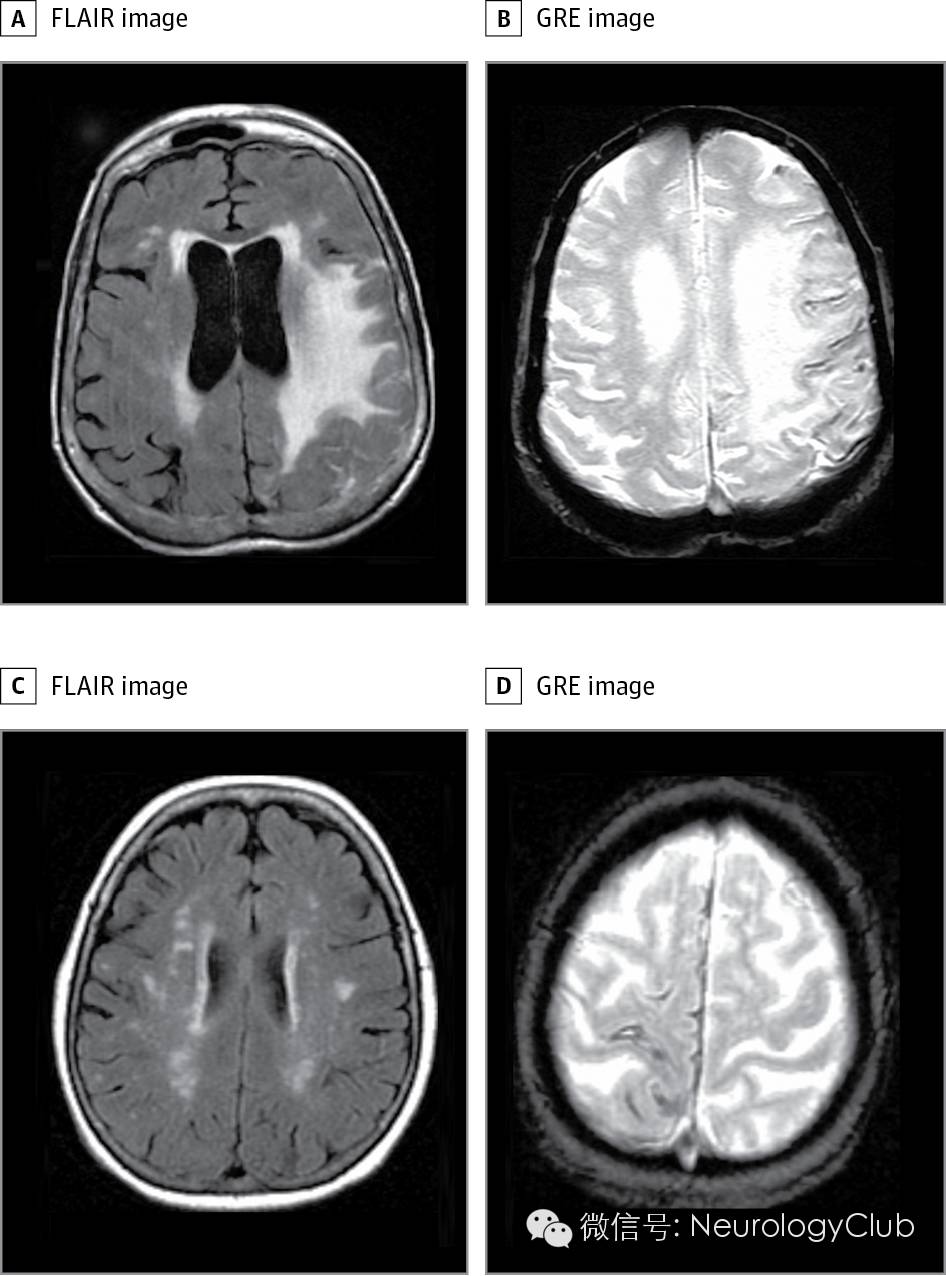

(A-B:75岁女性;C-D:80岁女性;两例患者梯度回波序列上均可见皮层表面铁沉积;A符合很可能的CAA-I的诊断标准;C符合可能的CAA-I的诊断标准;